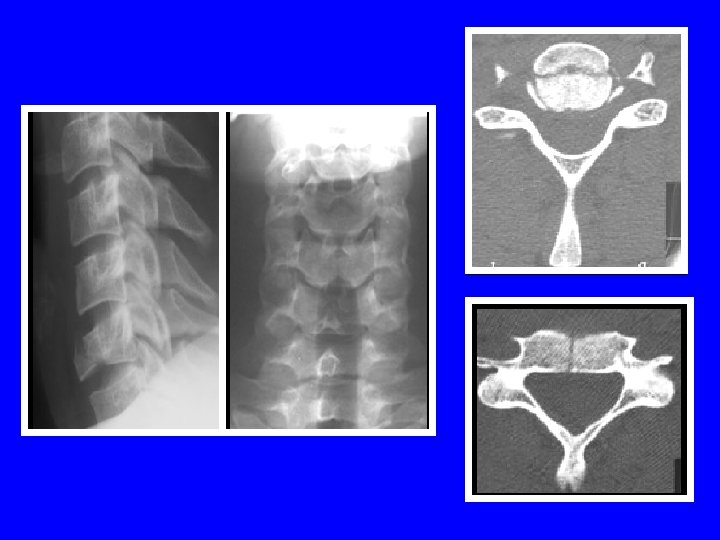

LESIONS MIXTES: LA FRACTURE TEAR DROP Schneider et Kahn (1956) Mécanisme en flexioncompression trait de fracture frontal trait de fracture sagittal trait de fracture lamaire lésions ligamentaires LLV, LLD, disque

Prédomine en C 5 (65%) Neuroagressivité++ stade 3 de Allen: 25% (médullaire) stade 5 de Allen: 91% (médullaire) Instabilité selon l ’atteinte discoligamentaire Les disques sus et sous-jacents peuvent être atteints Double tear drop

LESIONS MIXTES: LA FRACTURE TEAR DROP Allen (1986): 5 stades stade 1: aspect émoussé du coin antéro-inférieur stade 2: perte de hauteur partie antérieure du corps stade 3: trait de fracture en goutte d ’eau stade 4: stade 3+ déplacement postérieur <3 mm stade 5: stade 3+ déplacement postérieur >3 mm

Tear drop stade 3 Tear drop stade 4